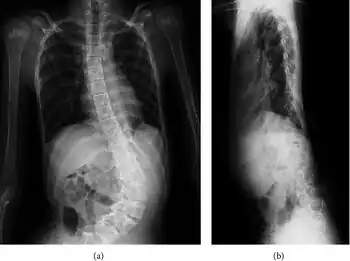

a) X-ray—anterior-posterior view of levoscoliosis b) X-ray—lateral view.

People with Shprintzen-Goldberg syndrome can experience a range of symptoms that vary in severity. Due to craniosynostosis, people with SGS may have a long and narrow head, wide spaced protruding eyes that may slant downwards, a high and narrow palate, a high and prominent forehead, a small lower jaw, and low-set posteriorly-rotated ears. Some other skeletal abnormalities people with SGS may experience include joint hypermobility, clubfoot, scoliosis, camptodactyly, arachnodactyly, long limbs, and a chest which appears to sink in or stick out. Other symptoms that may be experienced include brain abnormalities (i.e. hydrocephalus), developmental delays, intellectual disability, gastrointestinal problems (i.e. constipation, gastroparesis), abdominal or umbilical hernias, easily bruised skin, trouble breathing, and hypotonia. Some cardiac issues which are occasionally seen in people with SGS include aortic aneurysm, aortic regurgitation, aortic root dilation, mitral valve regurgitation, and mitral valve prolapse.[4]